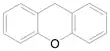

Xanthene-based sensitizers

Xanthene-based sensitizers, on the other hand, have shown successful cytotoxicity in vitro by producing reactive oxygen species after being triggered by ultrasound.[1] More research is necessary to improve its potential in vivo performance since it is quickly processed by the liver and cleared from the body.[1] Rose Bengal is a commonly used xanthene-based sonosensitizer.[1]